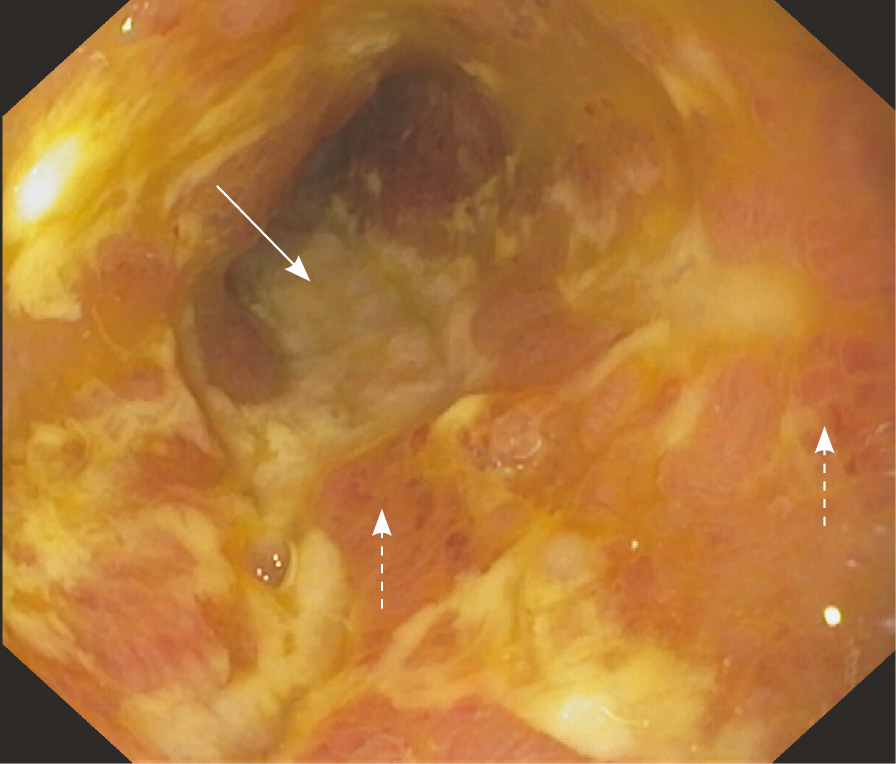

В условиях хирургического отделения СПбГБУЗ «Городская клиническая больница № 31» 02.03.2023 пациенту выполнена резекция слепой кишки, 100 см подвздошной кишки с формированием илеоасцендоанастомоза по поводу множественных стриктур подвздошной кишки (рис. 3). Последнее введение канакинумаба выполнено 10.03.2024.

Рис. 3. Фото операционного материала. Препарат тонкой кишки со стриктурами и феноменом «ползучий жир»